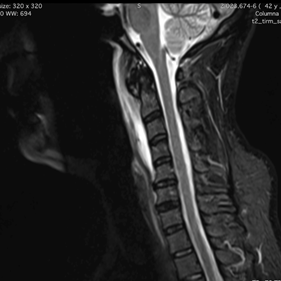

Se solicitó TAC urgente que identificó un aumento del espacio prevertebral, con la presencia de gran calcificación que se extendía anteriormente desde sector inferior al arco del Atlas hasta la base de la apófisis odontoides; orientando al diagnóstico de tendinitis calcificante del músculo largo del cuello. Se realiza además de forma urgente RNM de cuello, donde se evidencia extensa imagen hiperintensa retrofaríngea en relación directa con calcificación antes descripta, llegando hasta sector anterior nivel de C5.

Figura 4: RNM columna cervical de nuestro caso problema, secuencia T2; donde se visualiza una señal hiperintensa prevertebral, correspondiente a una colección líquida extensa, edematosa, desde base del cráneo hasta sector anterior del cuerpo de C5. Además se constata grosera calcificación a nivel anterior de C1-C2.